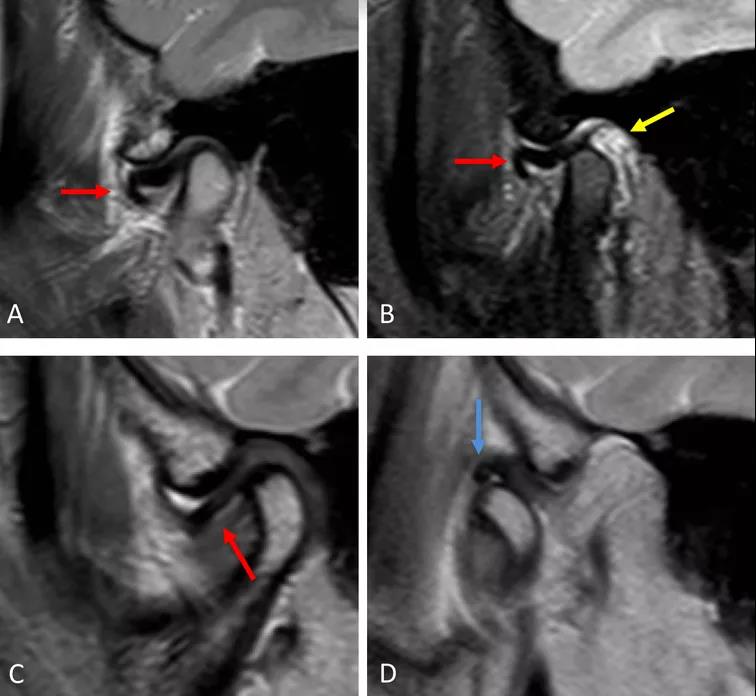

病例一:斜矢狀平面上的質(zhì)子密度加權(quán)圖像(PDWI)

A圖示:閉口位時(shí),顯示關(guān)節(jié)盤(pán)前移位明顯,雙凹形態(tài)消失。注意前帶的下移位(紅色箭頭)。

B圖示:張口位時(shí),顯示關(guān)節(jié)盤(pán)移位(紅色箭頭),關(guān)節(jié)積液(黃色箭頭)。病例2:斜矢狀平面上的質(zhì)子密度加權(quán)圖像(PDWI)

A圖示:閉口位時(shí),顯示下頜骨髁突前上側(cè)面硬化,前方扁平的椎間盤(pán)移位(紅色箭頭)。